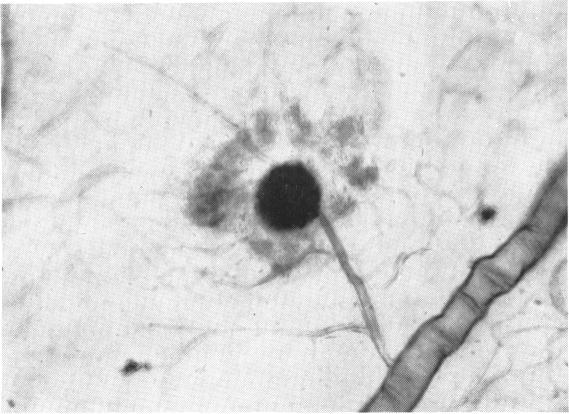

Vascular changes in diabetes with particular reference to the retinal vessels; preliminary report.

Br J Ophthalmol. 1949 Jul;33(7):407-20. doi: 10.1136/bjo.33.7.407.